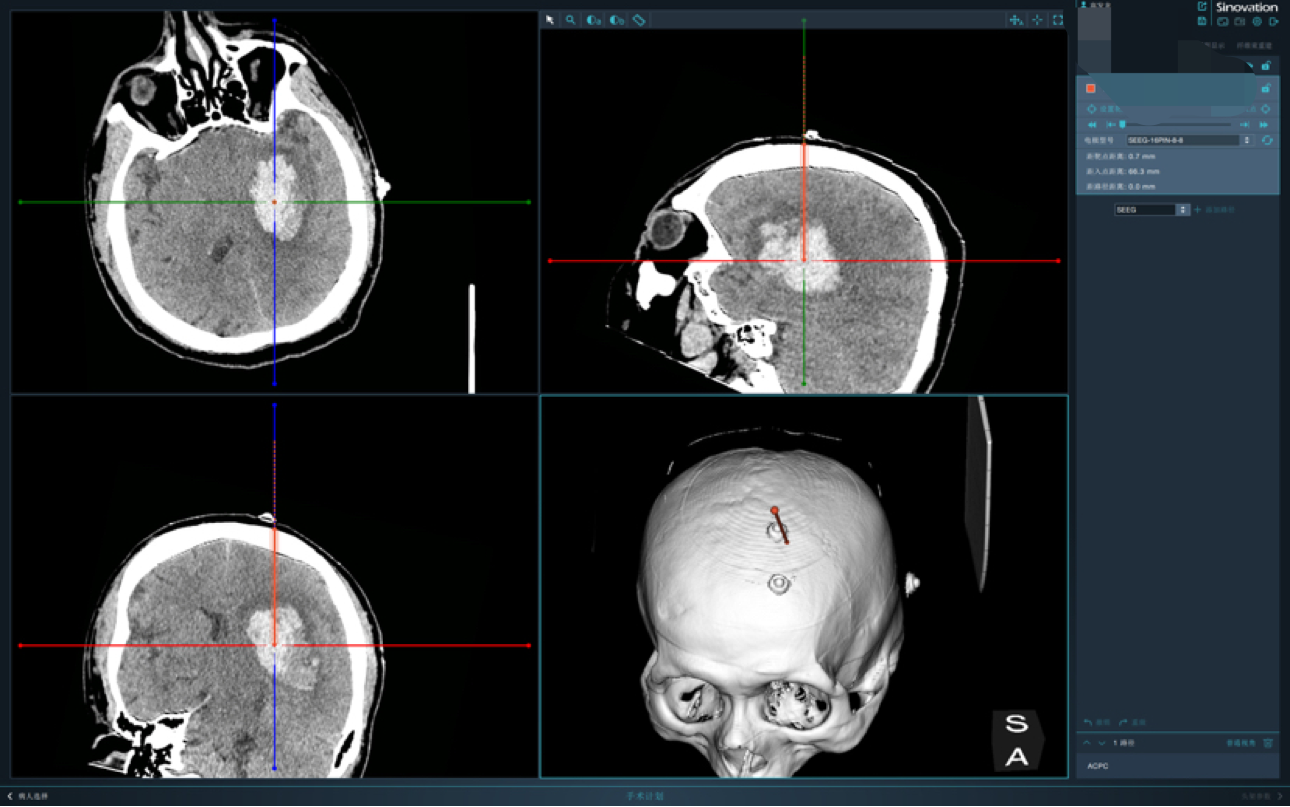

毫米级精度:机器人系统实现亚毫米级血肿定位,减少脑组织损伤。

极速微创手术:0.5cm切口,0.3cm骨孔,10分钟手术,2ml出血量。

智能化平台:集成震颤过滤、多自由度机械臂等技术,突破传统手术局限。